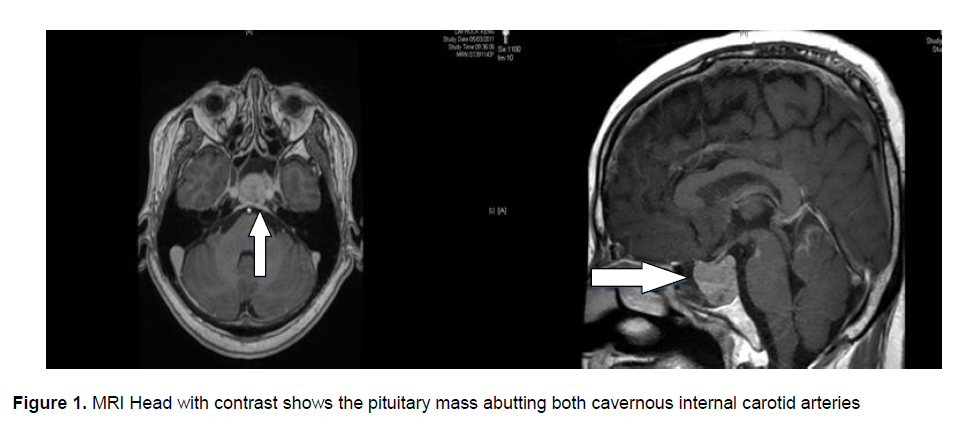

He was diagnosed with disseminated pneumococcal disease, complicated by diabetic ketoacidosis. He received 2 weeks of ceftriaxone and crystalline penicillin. His blood glucose levels were closely monitored and his insulin infusion was adjusted accordingly. A Magnetic Resonance Imaging (MRI) of his head with contrast was performed to ensure no interval progression on Day 5 of admission. Instead, an incidental pituitary mass was noted (Figure 1). Prolactin level was 12867 ng/dL. Apart from low testosterone levels, the other hormone levels were within normal range.

Figure 1. MRI Head with contrast shows the pituitary mass abutting both cavernous internal carotid arteries